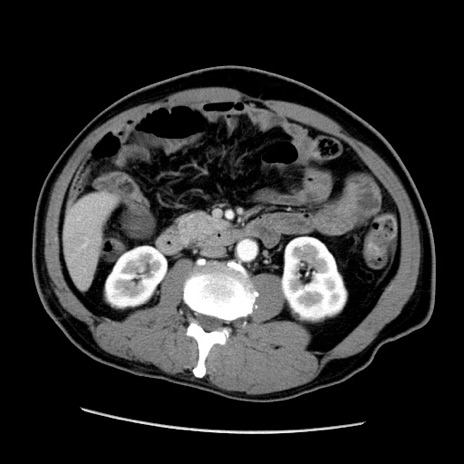

症例22(横断像)

【症例】50歳代男性

【主訴】腹痛

【現病歴】AVMからの被殻出血のため回復期リハ病棟入院中。 本日午後3時頃急に下腹部痛が出現した。

【既往歴】AVM、被殻出血、虫垂炎、高血圧

【身体所見】意識晴明、左半身不全麻痺、会話の理解は良好、36.5°C、腹部:膨隆、全体に板状硬、下腹部正中に圧痛点あり、反跳痛-、筋性防御不明、右下腹部にope scar

【データ】WBC 9400、CRP 0.06